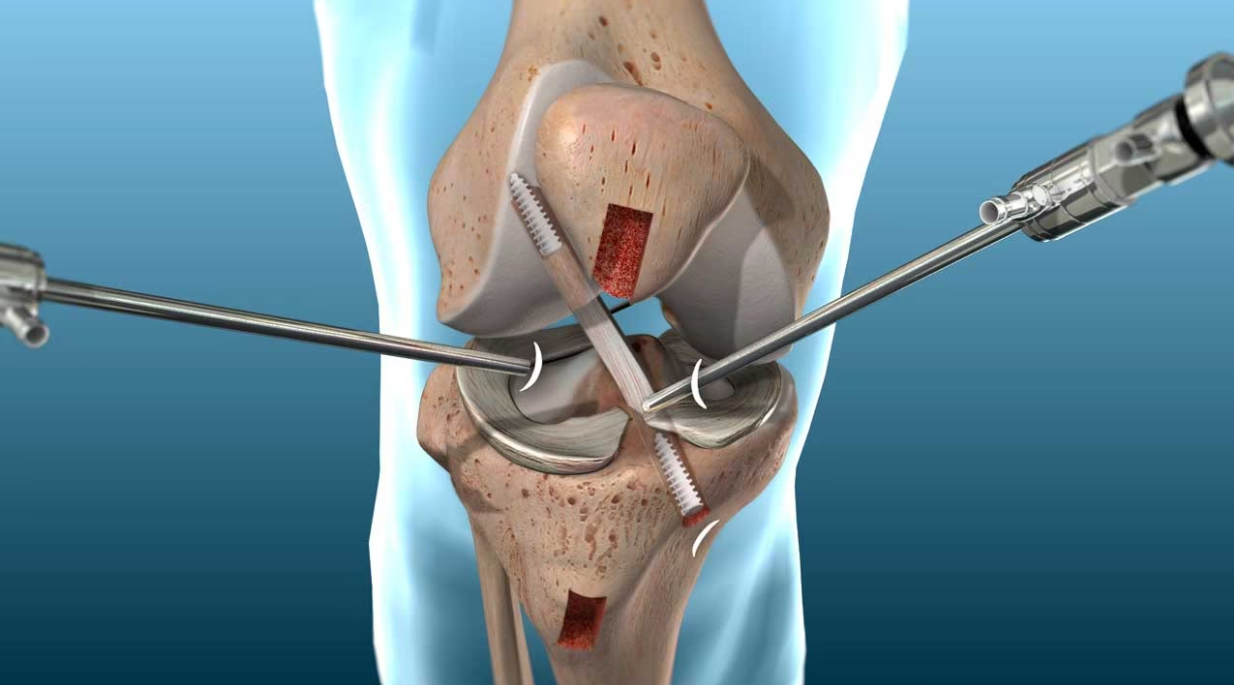

Minimally Invasive Procedure: Our arthroscopic approach minimizes tissue damage, leading to quicker recovery times and less postoperative discomfort compared to traditional surgery.